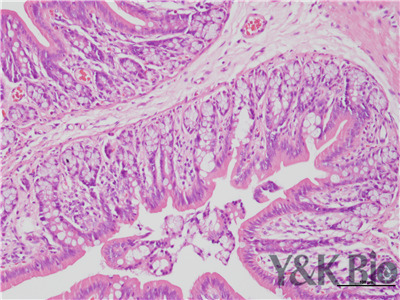

HE染色是病理染色服务中不可缺少的染色项目之一,陕西依科生物多年来一直从事病理染色服务。HE染色法是组织学、胚胎学、病理学教学与科研中较基本、使用广泛的技术方法。这种方法对组织细胞的各种成分都可着色,经过HE染色,细胞核被苏木素染成蓝紫色,细胞质被伊红染色呈粉红色。苏木素是碱性染料,蓝紫色,可以使细胞核等着色。被苏木素着色的结构本身为酸性,具有嗜碱性(Basophilic)。伊红是酸性染料,粉红色。可以将大多数细胞的细胞质染成红色。被伊红着色的结构本身为碱性,具有嗜酸性(Acidophilic)。